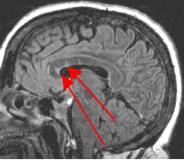

Fig. 2

By turning CSF dark, bright periventricular lesions such as MS plaques become much more conspicuous. Fig. 1 shows a typical T2-weighted axial image of the brain in which CSF in the ventricles appears bright. A lesion on the right is present (red arrow) that is also bright similar to CSF. Fig. 2 is a corresponding FLAIR image showing an obvious bright MS plaque (white arrow) against a background of dark CSF and gray parenchyma with additional more subtle lesions.